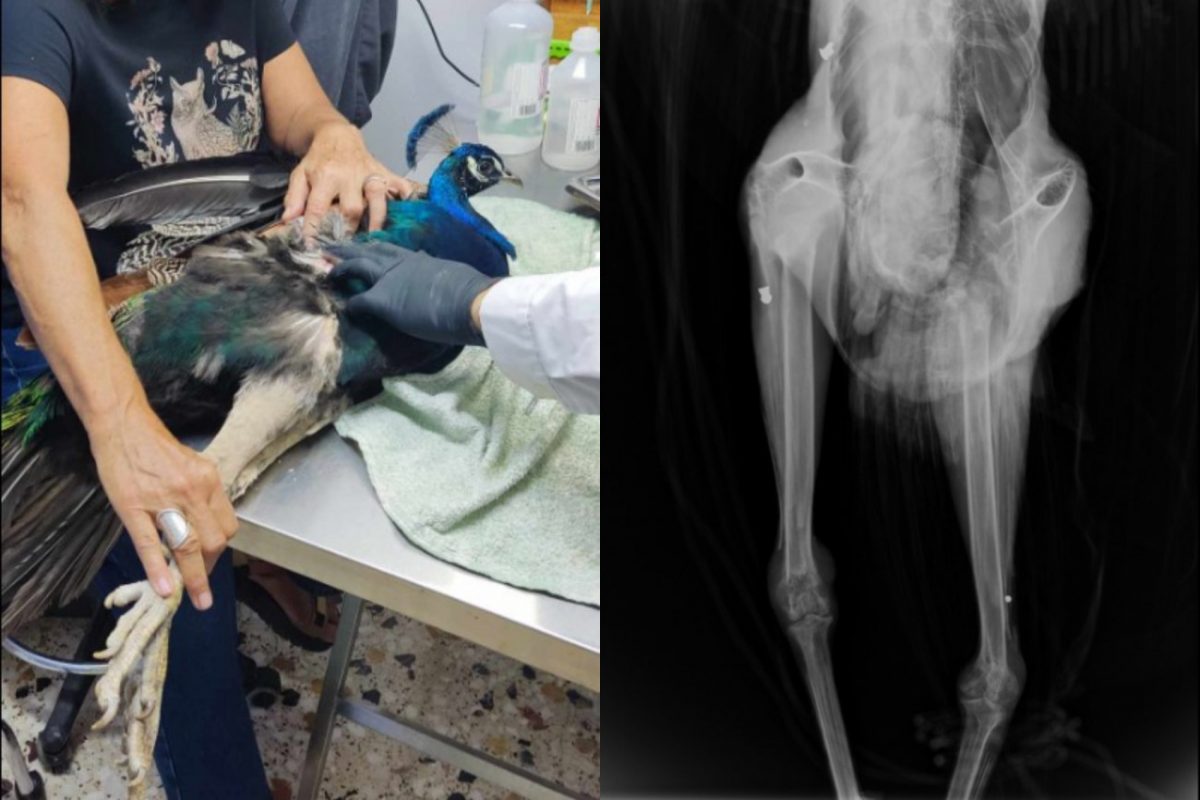

Ηράκλειο: Άγνωστοι πυροβόλησαν το παγώνι της Κνωσού – Του έγινε ακτινογραφία επειδή κούτσαινε

«Το παγώνι έχει πυροβοληθεί τρεις φορές, προς έκπληξή μας στην ακτινογραφία είδαμε δυο βολίδες αεροβόλου κι ένα σκάγι» αναφέρεται σε ανάρτηση του συλλόγου ΑΝΙΜΑ

Το παγώνι της Κνωσσού πυροβόλησαν άγνωστοι στην Κρήτη, όπως έδειξε ακτινογραφία που έγινε από τον σύλλογο ΑΝΙΜΑ που ανέλαβε να το περιθάλψει επειδή κούτσαινε και είχε προβληματίσει τους υπευθύνους του αρχαιολογικού χώρου.

Όπως αναφέρει συγκεκριμένα ο Σύλλογος Προστασίας και Περίθαλψης Άγριας Ζωής ΑΝΙΜΑ, ένα παγώνι που κούτσαινε εδώ και λίγο καιρό στάλθηκε σε αυτούς από τον αρχαιολογικό χώρο της Κνωσού μέσω του Μουσείου Φυσικής Ιστορίας Κρήτης.

Σε σχετική ανάρτηση του συλλόγου στο Facebook σημειώνεται: «Με έκπληξή μας, εμφανίζοντας την ακτινογραφία, είδαμε δυο βολίδες αεροβόλου κι ένα σκάγι μέσα στο σώμα του. Το ζώο αυτό έχει πυροβοληθεί τρεις φορές, την ίδια ώρα ή διαφορετικές δεν μπορούμε να ξέρουμε, ούτε αν ο δράστης είναι ένας ή δύο ή τρεις, μέσα ή δίπλα σε έναν από τους πιο πολυσύχναστους αρχαιολογικούς χώρους της Κρήτης και της Ελλάδας γενικότερα».

Η ακτινογραφία που έγινε στο παγώνι επειδή κούτσαινε αποκάλυψε τη φρίκη

Σύμφωνα με το Cretapost, το θλιβερό περιστατικό έχει προκαλέσει ανησυχία, καθώς συνέβη σε έναν από τους πιο πολυσύχναστους αρχαιολογικούς χώρους της Κρήτης και γι’ αυτό απαιτεί άμεση διερεύνηση από τις αρμόδιες Αρχές.